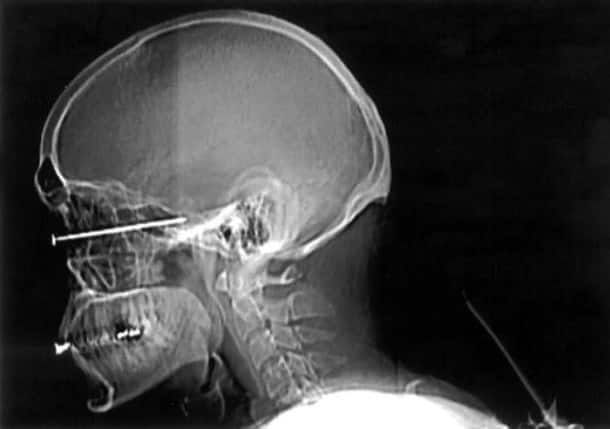

33 radiographies qui prouvent que les gens font des choses douteuses avec leur corps !